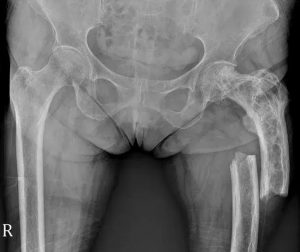

Fig. 1 AP view of the hip and femur.

Fig. 2 Annotated image showing Paget's Disease with cortical thickening, trabecular accentuation, osseous expansion and femoral fracture

Pathological fracture of the left femur secondary to Paget disease. Paget disease has remodeled the osseous structure to demonstrate cortical thickening, trabecular accentuation, and osseous expansion. This weakened bone is now susceptible to a pathological fracture that will typically take on a transverse orientation.